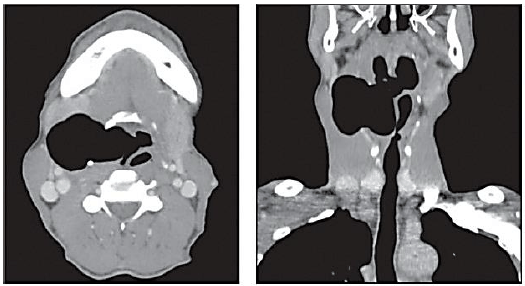

Homem, 60 anos, com história de massa cervical indolor de crescimento progressivo há nove meses, acompanhada de rouquidão. Nega dispneia; disfagia; perda ponderal; febre; ou, outros sintomas. Exame ultrassonográfico teve como laudo massa com superfície de reflexão intensa, de difícil caracterização, sugestiva de presença de gás em seu interior. Realizada aspiração por agulha fina da lesão, cujo laudo descrevia apenas material insatisfatório. Posteriormente, foi submetido à tomografia computadorizada, cujas imagens, em cortes axial e coronal, respectivamente, estão representadas a seguir:

Considerando a situação hipotética, o diagnóstico mais provável é: